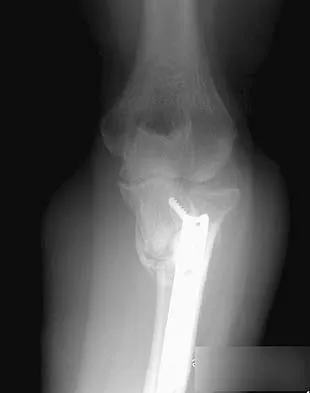

A 54-year-old woman sustained an elbow injury 3 months ago that was treated with open reduction and internal fixation. She now reports pain and limited elbow motion. Radiographs are shown in Figures 10a and 10b. Treatment should now consist of

Explanation

Radiographs reveal malunion of a Monteggia fracture-dislocation. Dislocation of the posterior radial head is caused by the malunited ulnar fracture. The deformity includes shortening with an apex posterior angulation. In the acute setting, open reduction of the radial head rarely is necessary; however, in chronic dislocations, open reduction is required. Without ulnar osteotomy, recurrent radial head dislocation is likely.